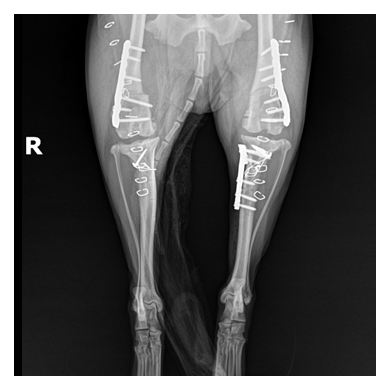

양측 슬개골 탈구

양측 4등급 슬개골 탈구 교정 (DFO) 및 좌측 십자인대 교정

정형외과 케이스

본원은 실력 있는 전문 의료진과 최첨단 시설로 정형외과에서 좋은 예후들을 보여드리고 있습니다. 강아지에게서 쉽게 발생하는 슬개골 탈구, 십자인대 단열 뿐 아니라 다양한 고난도 케이스를 다루고 있으며, 특히 골절 수술은 회복률이 높고 타원 수술 후, 유합부전으로 본원에 내원하여 재수술에 성공한 사례가 많습니다.